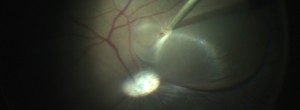

Retinal vein occlusions.

Optical Coherence Tomography Assessment of Apparent Foveal Swelling in Patients with Foveal Sparing Secondary to Geographic Atrophy.

GAIN. Characterization of geographic atrophy progression in patients with age-related macular degeneration: evolution and risk factors associated with geographic atrophy progression